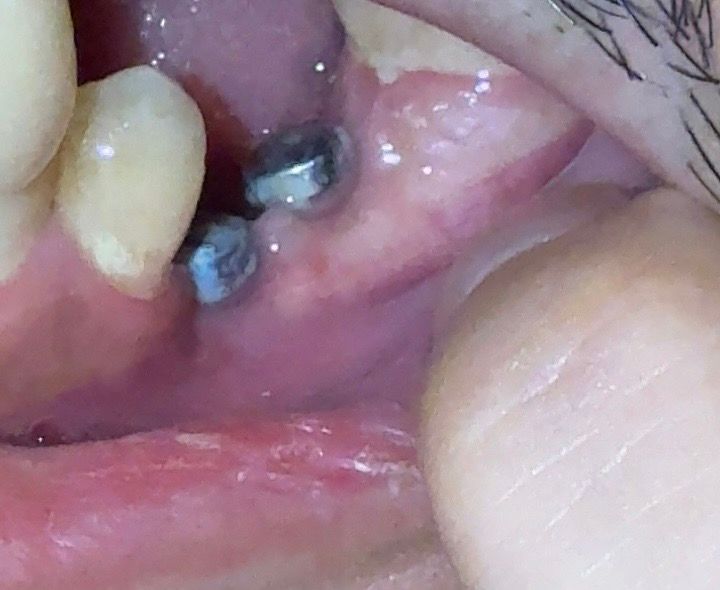

사진에서 보시면 아래쪽 잇몸이 많이 꺼져있는것 같은데 보철물 부착을 할 수 있는지 궁금합니다

• 2번 째 사진